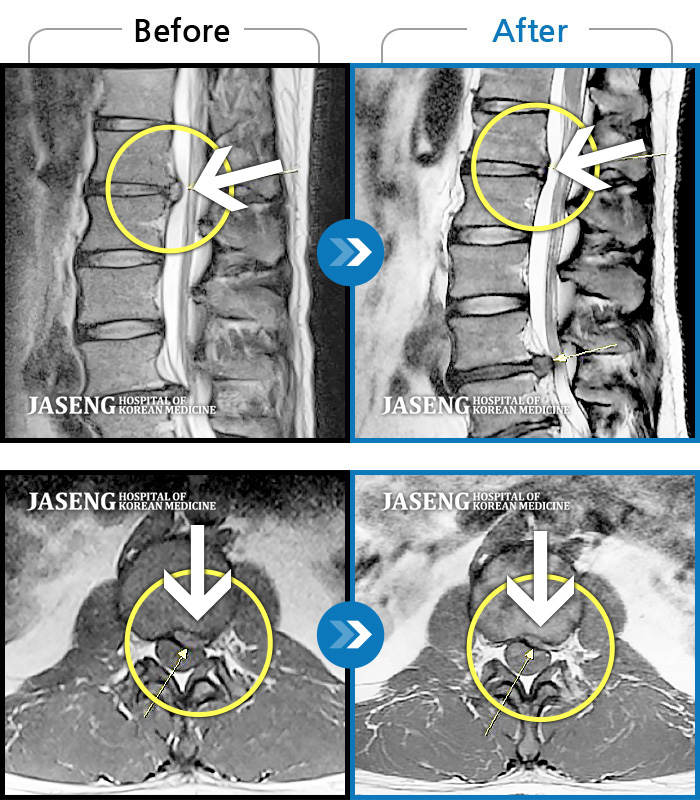

68 MRI ũ ʸ Ȯϼ.